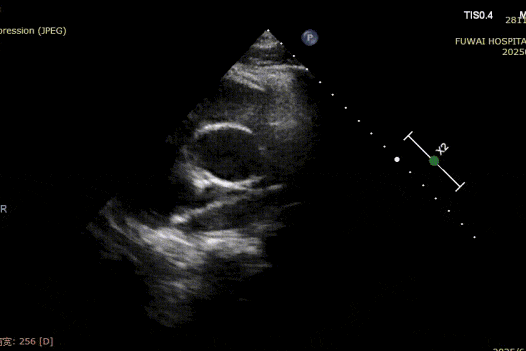

Dada la proximidad del defecto a la arteria coronaria, un oclusor metálico tradicional planteaba un riesgo de compresión, especialmente durante el esfuerzo físico. Por lo tanto, se seleccionó un oclusor de ASD biodegradable (BDASD-I 18mm) por su flexibilidad, menor riesgo de lesión mecánica a largo plazo y capacidad para degradarse en dióxido de carbono y agua después de completar la función de cierre.

1-day postoperative TTE revealed that the occluder is in good shape without residual shunt (see last figure).